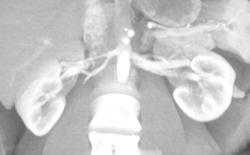

Transitional Cell Carcinoma-lower Pole of Right Kidney